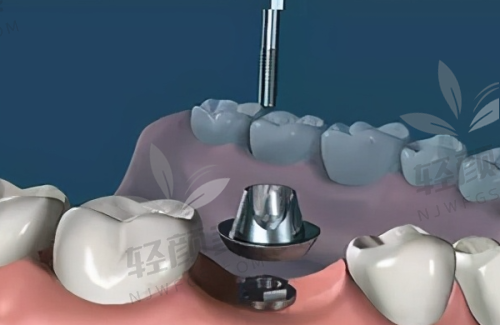

黎强医生真的特别亲切,他详细地询问了我的牙齿情况和病史,然后带我去做了全方面的口腔检查。检查设备都特别精良,整个过程也特别舒服。检查完之后,黎强医生给我分析了我的牙齿状况,耐心地给我讲解了穿颧穿翼种植牙的原理和过程。他说我的牙槽骨条件不太好,普通种植牙可能成效不佳,而穿颧穿翼种植牙可以利用颧骨和翼板的骨质,为种植体提供更稳定的支撑。我听了之后,心里踏实了不少。

黎强医生根据我的检查结果,为我制定了个性化的穿颧穿翼种植牙方案。他给我看了特别多类似实例的前后对比照片,让我对手术成效有了更直观的认识。我对方案特别满意,但是心里还是有点担心手术的风险和疼痛。黎强医生看出了我的顾虑,他安慰我说,穿颧穿翼种植牙技术已经特别成熟了,他做过特别多这样的手术,成功几率非常高。而且手术过程中会使用精良的麻醉技术,不会让我感觉到疼痛。听了他的话,我心里的石头终于落了地。